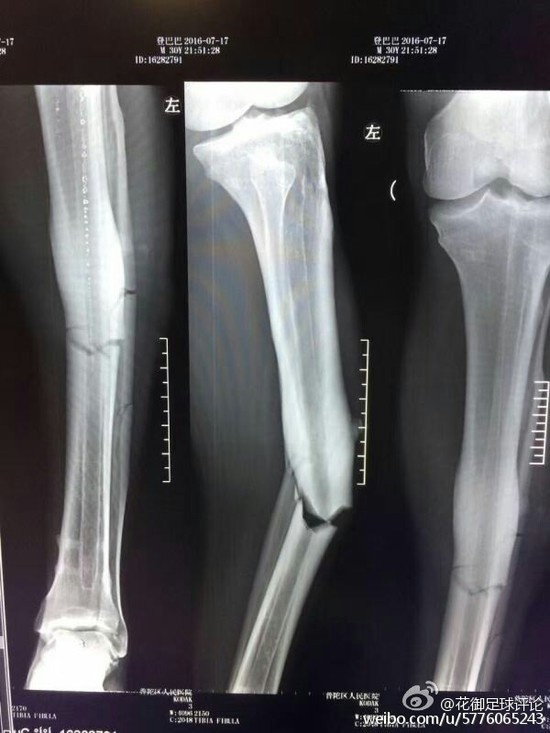

左腓骨骨折 治療-左侧腓骨远端骨折怎么治疗? 检查方法:左踝关节正侧位X线表现左踝关节在位,关节面光滑,关节间隙未见明显狭窄,左侧腓骨远端见透亮影,余骨未见明显骨折征象。 结论考虑左侧腓骨远端骨折是个女孩17了。 溜冰时摔倒 X线表现 左踝关节在位,关节面光滑,关节间隙未见明显狭窄,左侧腓骨远端见透亮影,余骨未见明显骨折征象。 是个女孩 17了。 溜冰时摔倒的 病案1:男性, 岁。左小腿外伤19小时就诊, 查体 左小腿畸形, 假关节活动, 骨摩擦感,胫前伤口3cm, 骨端外露, x线显示左胫骨中段粉碎性骨折, 临床诊断 左胫骨中段开放性粉碎性骨折, 正确的急诊治疗 a 急诊手术, 钢板螺钉内固定 b 清创缝合, 小夹板固定 c 伤口

胫腓骨骨折在长管状骨 骨折中最常见。 胫腓骨干骨折 胫骨浅居皮下,缺乏肌肉附盖,故骨折后极易被骨折断端穿破皮肤。 多见儿童和青壮年。多为直接暴力所致。若发生在中下段,易引起延迟愈合或不愈合。 重定不好会产生创伤性关节炎。 腓骨骨折は転倒・転落で足首を強打した又は強く捻った際などに足首付近(外くるぶしの上下)で起こる事が多く、受傷すると痛みにより歩行困難となります。 単純に骨折しているだけでなく、脛骨と腓骨、腓骨と足部の靭帯も損傷している可能性もあるので、受傷後は必ず整形外科に受診しましょう。 腓骨骨折の診断 骨折はレントゲンにて診断可能です。 しかし、精査が必要な場